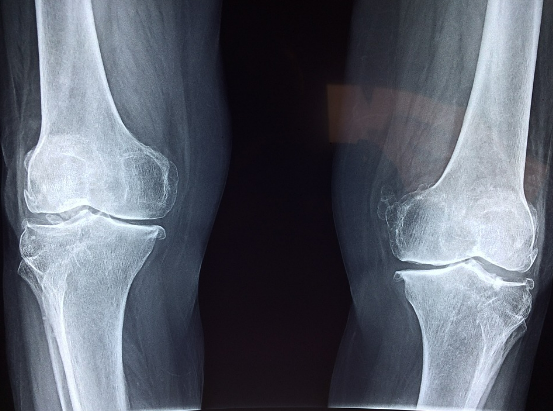

류마티스관절염은 관절통과 부종을 유발하는 자가면역질환입니다. 류마티스 관절염의 영향을 받은 관절은 시간이 지남에 따라 변형될 수 있으며 환자는 영향을 받은 팔다리를 움직이는 데 어려움을 겪을 수 있습니다. RA는 또한 몸 전체에 염증을 일으켜 심부전이나 피부 발진과 같은 다른 문제를 일으킬 수 있습니다. 류마티스 관절염은 잘못된 면역 체계가 자신의 세포를 공격하여 발생합니다. 이 상태의 정확한 원인은 알려져 있지 않지만 유전학 및 환경 요인이 발달에 기여할 수 있습니다. 류마티스 관절염은 조기 진단을 통해 효과적인 치료가 가능합니다.

관절 통증은 류마티스 관절염의 가장 흔한 증상 중 하나입니다. RA 환자는 관절에 염증(부기)이 있어 통증, 뻣뻣함 및 운동성 상실을 유발합니다. 손가락과 발가락의 붓기도 발생할 수 있습니다. 눈, 심장, 폐 또는 신장과 같은 다른 기관의 염증도 가능하지만 덜 일반적입니다.